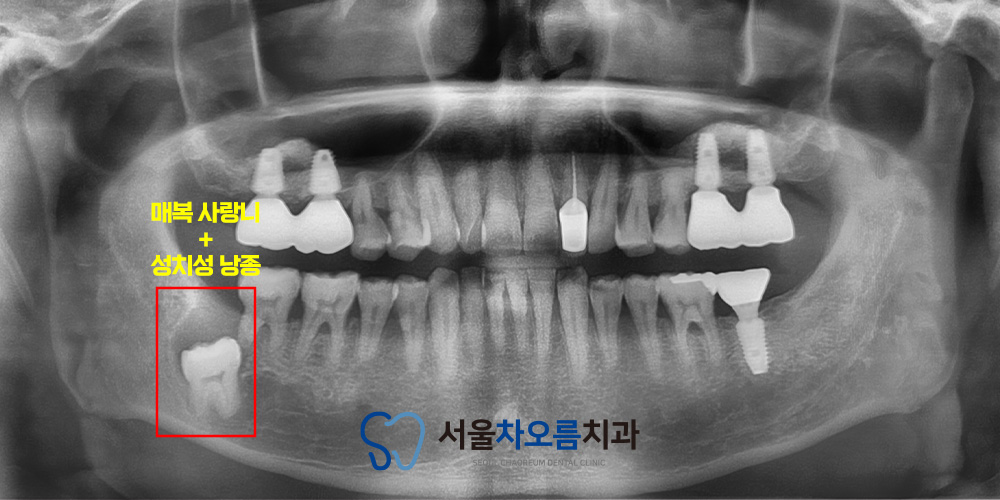

파노라마 촬영 결과,

오른쪽 아래 사랑니가

뼈 속 깊숙이 매복되어 있는 것이

확인되었습니다.

일반적으로 매복된 사랑니가

문제를 일으키지 않는다면

굳이 발치를 하지 않아도 되지만,

이 환자분의 경우 사랑니 주변에서

성치성 낭종이 발견되었습니다.

현재 자각 증상은 없었으나,

낭종이 점차 커질 가능성이 있고

주변 치아의 뿌리나 뼈를

손상시킬 위험이 있어

사랑니 발치와 함께

낭종 제거를 권유드렸습니다.

또한, 낭종을 그대로 두면

앞쪽 치아까지 영향을 미쳐

추후 발치로 이어질 수 있다는 점을 설명드린 후,